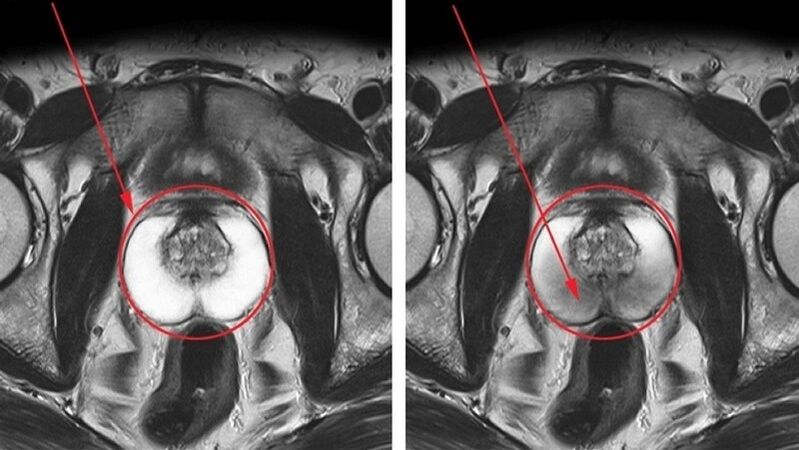

terve ja põletikuline eesnääre koos kroonilise prostatiidiga